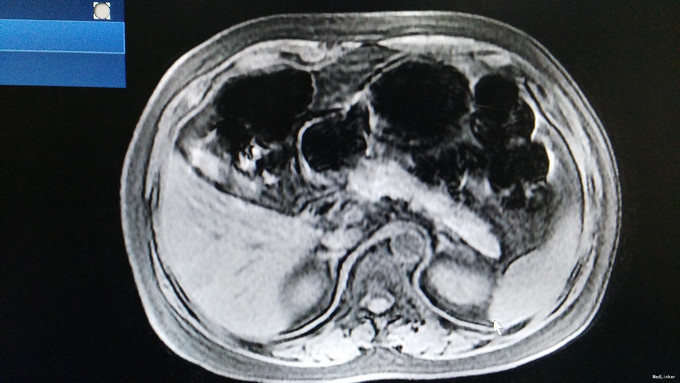

诊断为:低血糖症, .治疗:针对低血糖症:监测血糖,防止患者因低血糖发生意外。 2.针对胰腺占位性病变(胰岛素瘤可能性大):建议转入胰腺外科手术治疗,病情变化随诊。